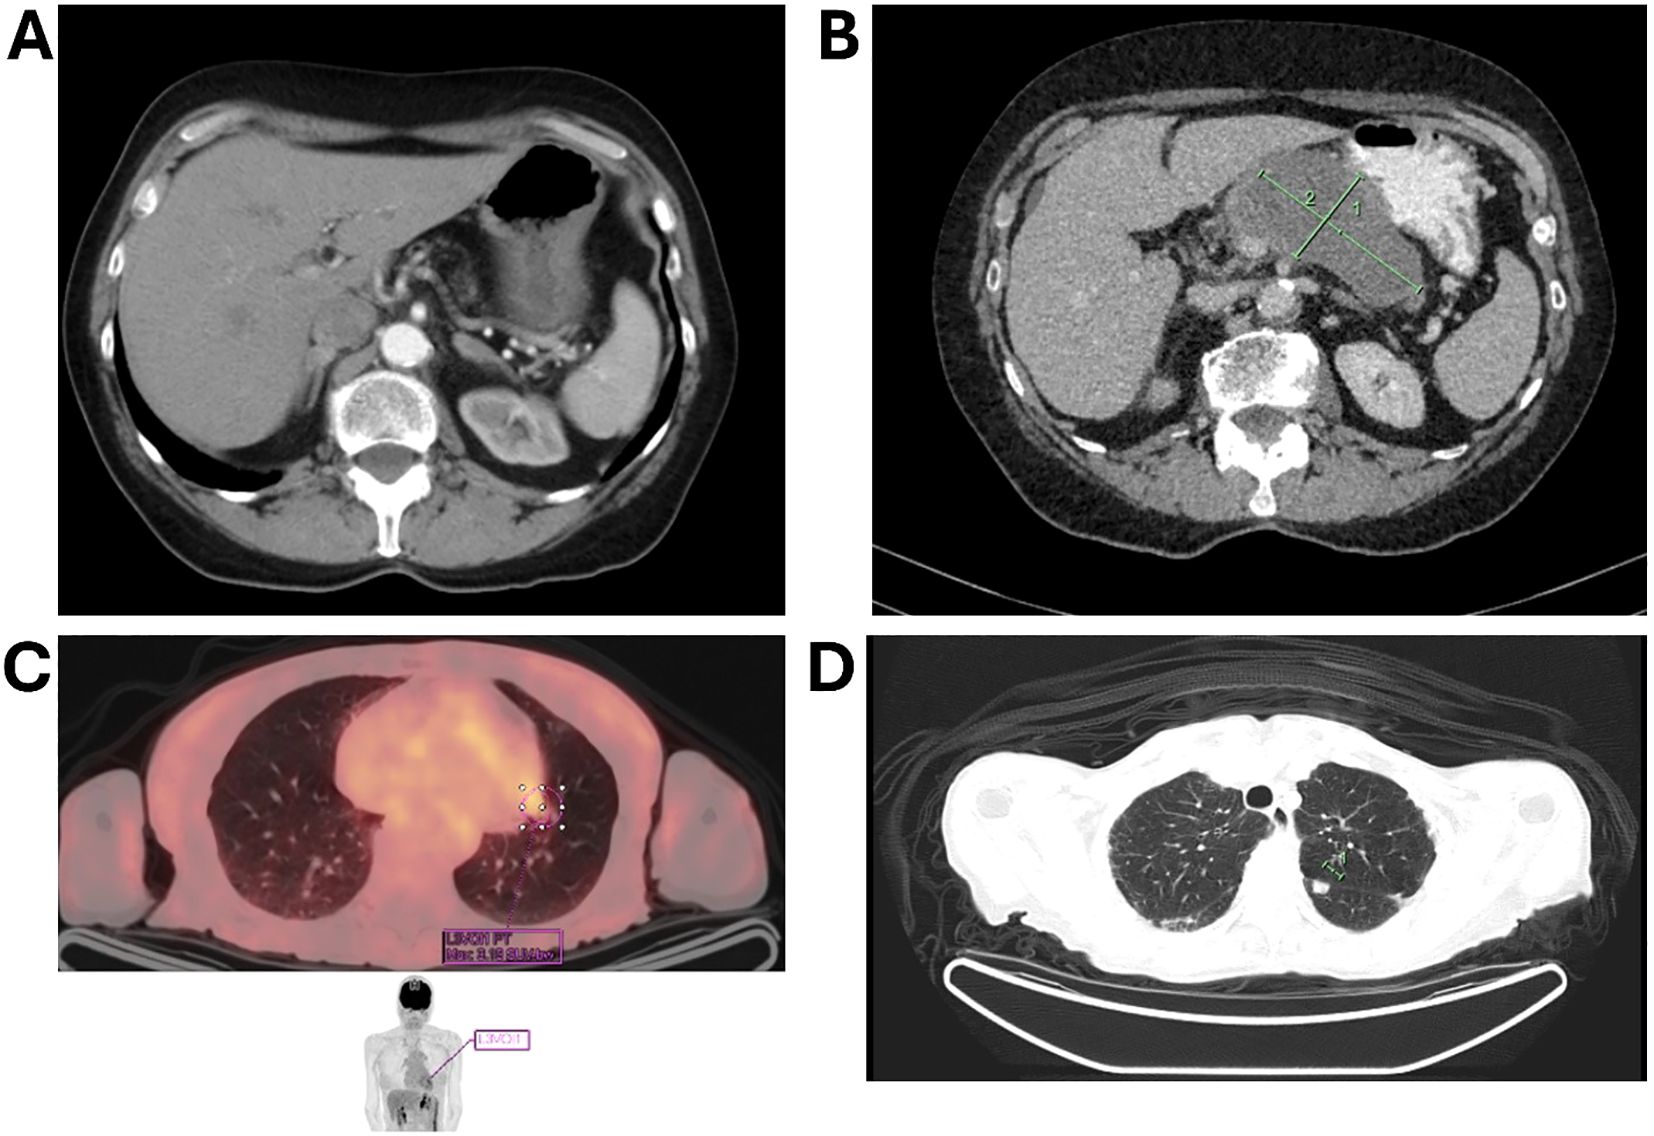

During routine follow-up, approximately 12 months after surgery (around 18 months from initial diagnosis), serial imaging and biomarker assessments showed disease progression. A solitary lung lesion was identified and successfully resected which was confirmed to be metastatic pancreatic cancer (Figure 1C). Later, a second pulmonary lesion was detected and treated with radiotherapy (Figure 1D), with subsequent imaging demonstrating a positive therapeutic response (Figure 2A). Despite these interventions, recurrence of the initial lung lesion occurred (Figure 2B), necessitating repeat radiotherapy, which again yielded a favorable response (Figure 2C). Eventually, new PET-avid pulmonary lesions were detected, coinciding with a rise in CA 19–9 levels, suggesting further disease progression.

CT scan images in axial view showing three different sections of the lungs. Panel A shows an upper thoracic section with visible lung fields and spinal column. Panels B and C show sections of the lower thoracic area with lung parenchyma and central airways. Each image highlights specific areas in the lung tissue.

Figure 2. (A) Follow-up imaging showing a good response to radiotherapy for the second lung lesion; (B) imaging depicting the recurrence of the first lung lesion; (C) subsequent imaging showing recurrence of the first lung lesion with a favorable response to radiotherapy.